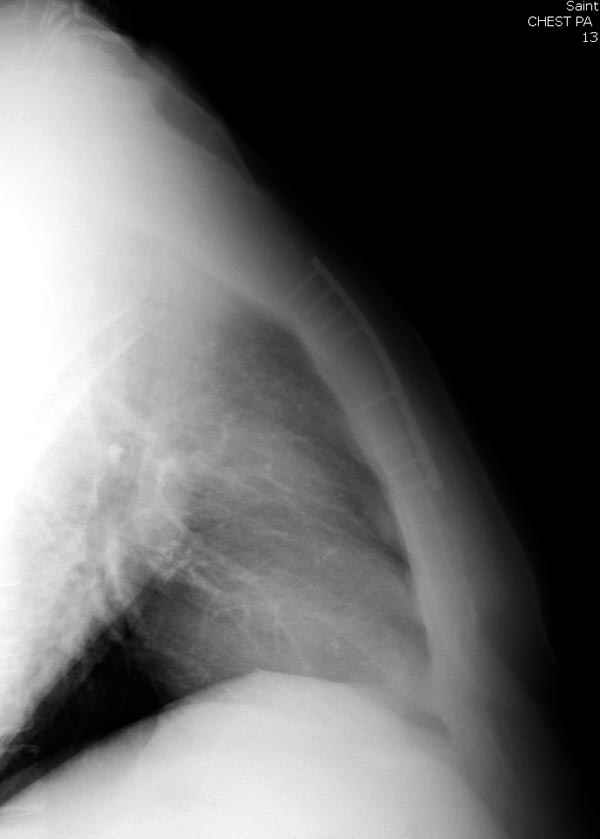

Пару лет назад коллега из грудной хирургии направил больного с хроническими жалобами на боли по поводу ложного сустава грудины.

Оперировали вместе с грудным хирургом и в нашем случае главной причиной была болезненность. Во время операции приняли все меры предосторожности недопущения прокола средостения (см. на 4 снимке близкий контур сердца!!)

Рентген снимки во время операции и последние сделаны на днях.